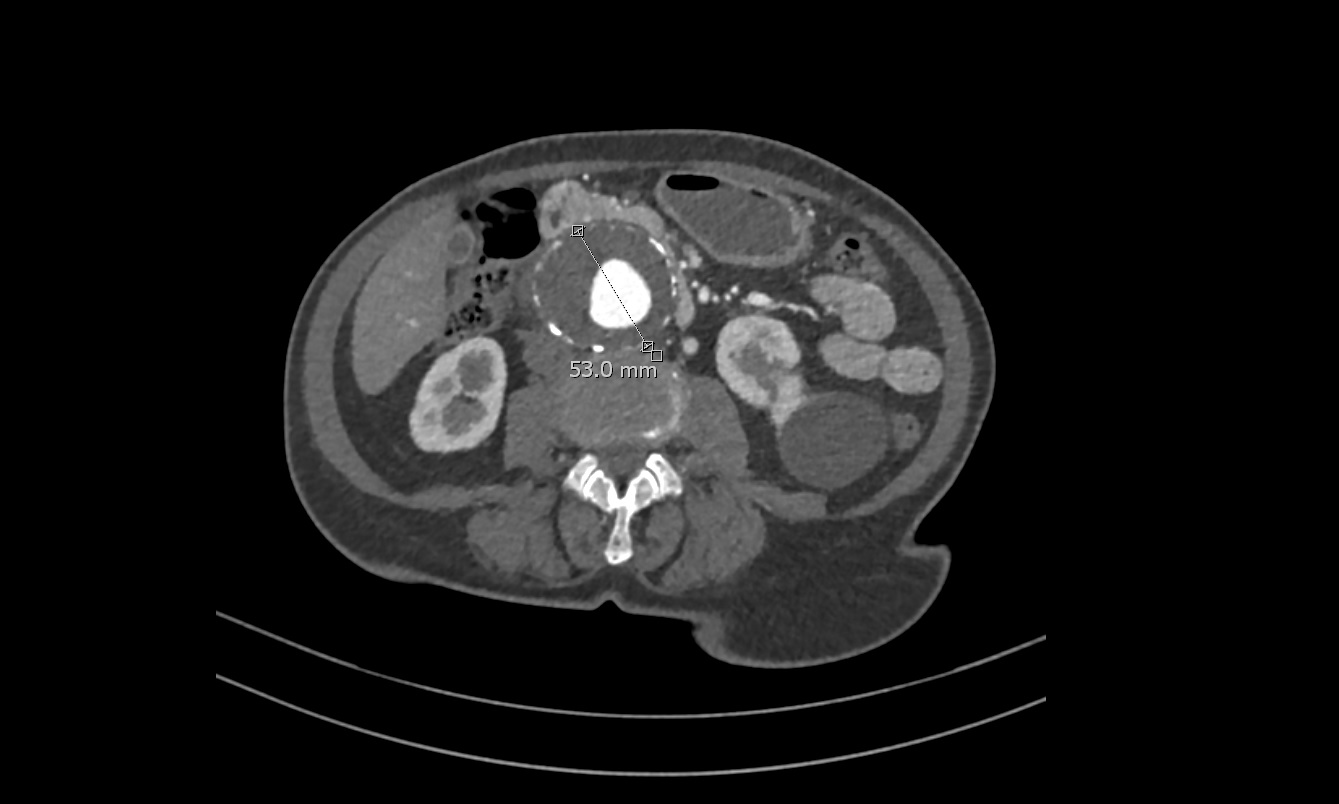

TC abdominal solicitado por Cirugía vascular confirma el diagnóstico de Aneurisma de Aorta Abdominal yuxtarenal de 9 cm de diámetro máximo, con trombo mural que se extiende distalmente hasta bifurcación de las arterias iliacas.